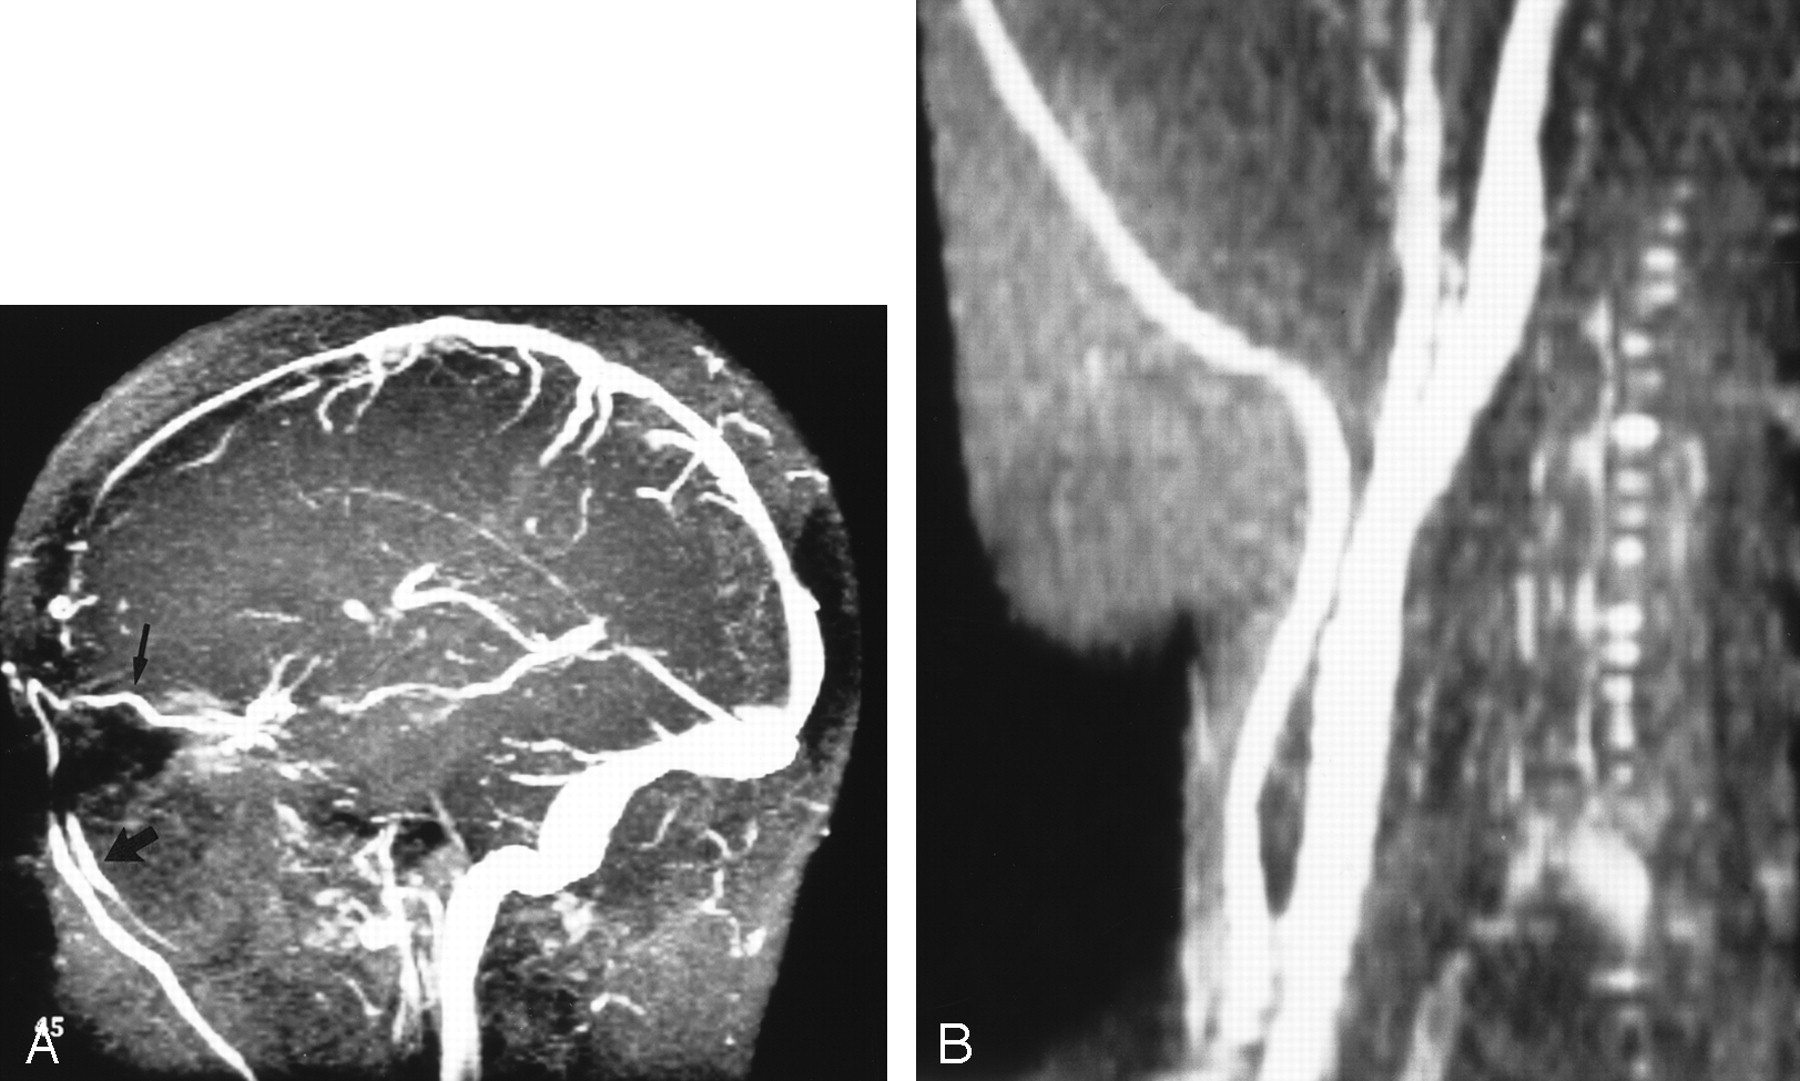

The SIH group had significant venous outflow obstruction. Five patients had focal thrombosis of the dominant transverse sinus; one, bilateral transverse sinus stenoses; and one, a very prominent arachnoid granulation that almost totally filled the posterior SSS. Figure 3 is an example of focal thrombosis, and Figure 4 shows bilateral stenoses. As would be expected, the mean SSS flow in the SIH group was reduced by 25% (P = .003), but the total blood flow was normal, indicating rapid autoregulation and rapid recruitment of venous collaterals.

Focal thrombus.

A, MR venogram (30/5/1 [TR/TE/NEX]) shows acute thrombosis of the transverse sinus. Arrow indicates area of signal intensity loss.

B, Sagittal reconstruction shows nonocclusive thrombus (arrow) just distal to the vein of Labbé.

Oblique view of the venous phase of cerebral angiography shows bilateral transverse sinus stenoses (arrows).